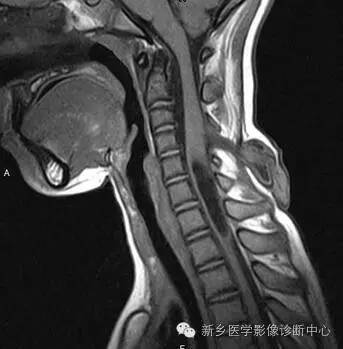

MR:

脊膜膨出:囊性肿块,与鞘膜囊想通;

脊髓脊膜膨出:囊性肿块内见脊髓或神经;

合并脊髓空洞,椎管脂肪瘤,脊髓低位,脊髓栓系,终丝粘连